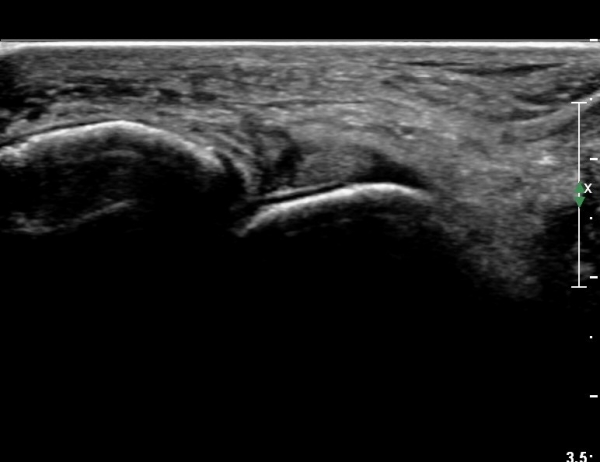

¹ß¸ñ À§¿¡¼­ ¸»´Ü ¾ÕÂÊ °æ°ñºñ°ñÀδë Á¾´Ü¸é°Ë»ç¿¡¼­ ƯÀÌ ¼Ò°ßÀ» º¸ÀÌÁö ¾Ê´Â´Ù(»çÁø 2, 3).